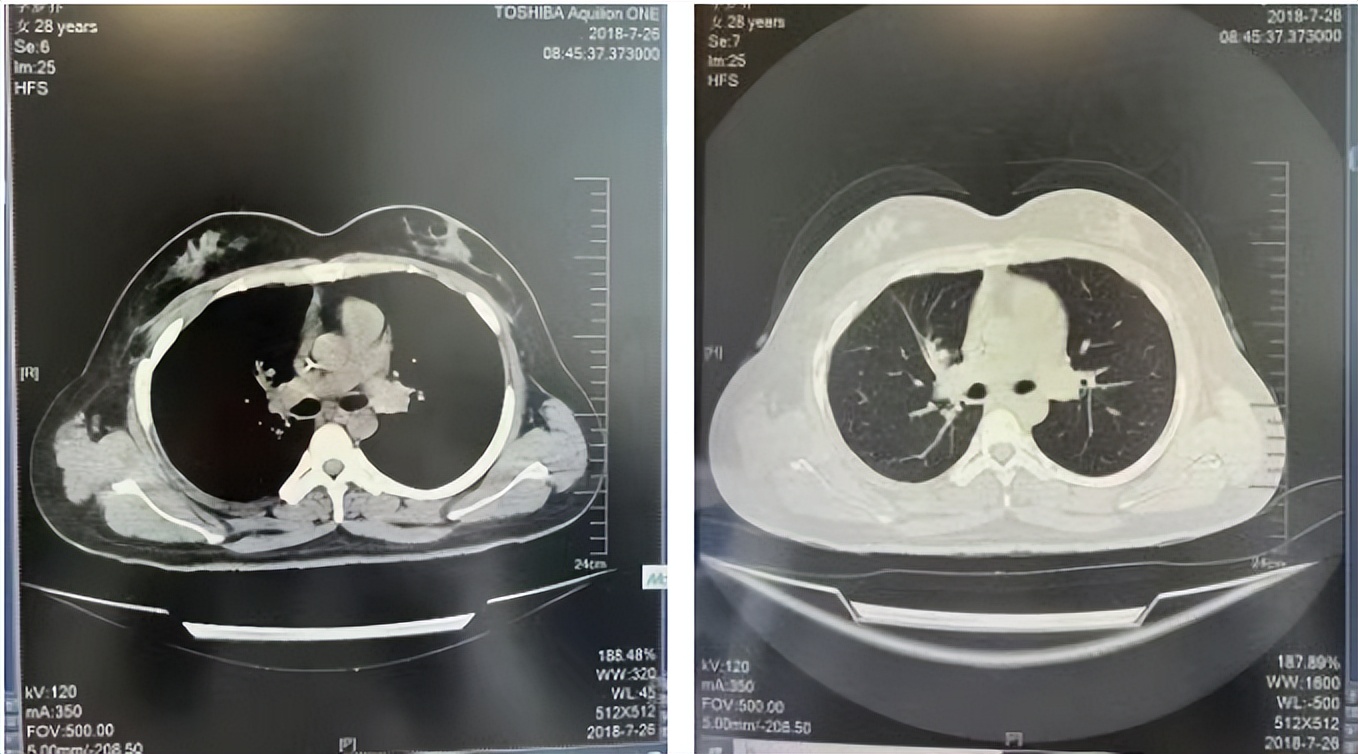

2016年1月复查CT提示支气管截断可见新发小结节,一线治疗采用培美曲塞+DDP方案化疗4周期(培美曲塞3.36,DDP 480mg)。化疗后复查胸部CT:右肺见不规则结节样影,最大层面大小约19mm*8mm,较前比较明显增大,疗效评估PD。2017.3-2017.4予单药多西他赛化疗3周期,疗效评估SD。2018年5月末复查CT提示结节较前增大,评效为PD,2018年6-10月予多西他赛+CBP化疗4周期,疗效评估SD。2022年5月患者出现活动后气短,复查胸部CT示右肺膨胀不良;右侧胸腔积液增多。胸腔积液包埋病理示符合肺腺癌细胞。行NGS基因检测:EML4:exon13-ALK:exon20融合。PD-L1(克隆号22C3)TPS<1%。

2018.07

2022.05